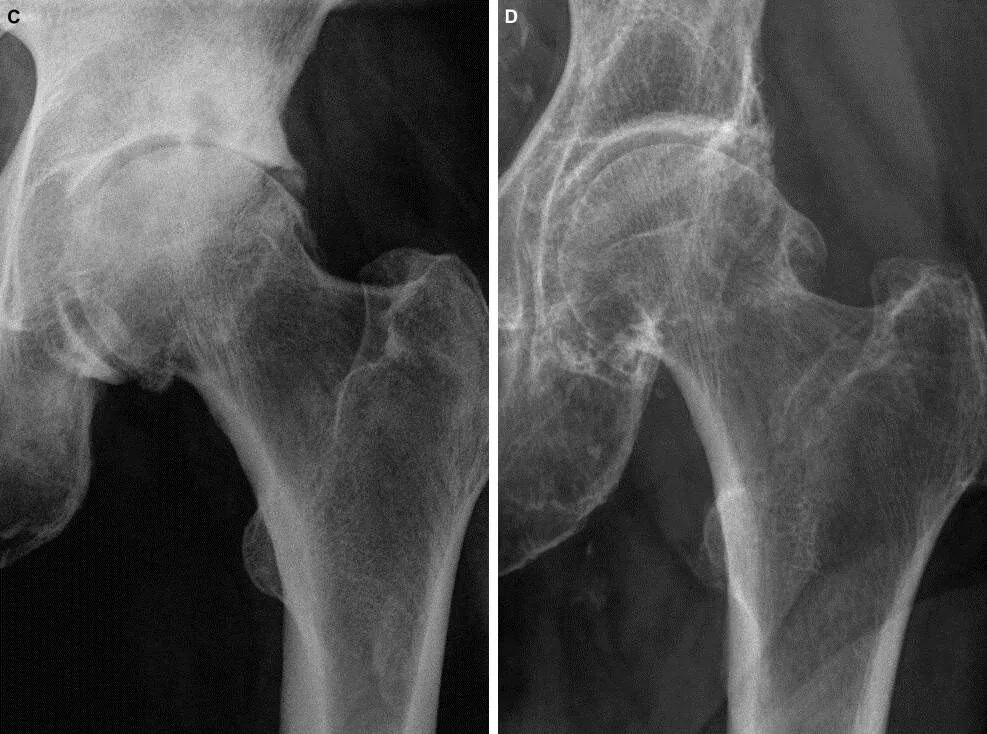

Артроз 2 степени симптомы